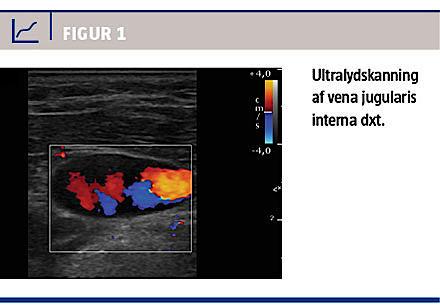

En 63-årig kvinde blev indlagt med henblik på elektiv fjernelse af et intrakranialt meningeom. Hun havde ikke tidligere haft tromboembolisk sygdom, og der var ingen familiær disposition. Anæstesiinduktion, venflon- og a-kanyleprocedure blev udført uden komplikationer. Anlæggelse af centralt venekateter (CVK) forud for operationen foregik ultralydvejledt. Ved aspiration fra CVK blev der observeret koagel. En ultralydskanning viste koageldannelser i lumen af v. jug. int. dxt. et sin. (Figur 1) og v. femoralis sin. et dxt. Et nyt CVK blev anlagt, men blodet koagulerede umiddelbart efter gennemskylning. Operationen blev derfor udskudt, og patienten blev udredt for trombofili inden fornyet planlagt operation.